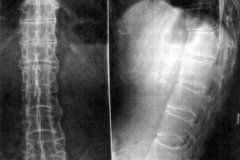

• 强直性脊柱炎通过X线检查能见到哪些改变

• 强直性脊柱炎X线检查有哪些表现